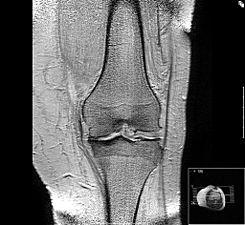

Desgaste de la articulación de la rodilla

La artrosis u osteoartritis es una enfermedad degenerativa crónica de lenta progresión común en la edad avanzada que afecta a las articulaciones móviles del cuerpo caracterizada por dolor articular, sensibilidad acentuada, rigidez, alteración en la movilidad, crepitaciones y derrame. Se genera a partir del daño acumulativo proveniente de lesiones microscópicas y macroscópicas en dichas articulaciones que activan una respuesta de reparación mal adaptada que incluye la activación de vías proinflamatorias del sistema inmunitario innato. El trastorno se manifiesta primero a nivel molecular y celular (metabolismo anormal de los tejidos de la articulación) seguido de alteraciones anatómicas o fisiológicas (degradación y pérdida del cartílago, remodelación del hueso, formación de osteofitos, inflamación sinovial, esclerosis y engrosamiento del hueso subcondral y pérdida de la función articular normal). El compromiso de la cadera y las rodillas son una causa común de discapacidad.12345

Las rodillas son las articulaciones sobre las que se carga la mayor parte del peso del cuerpo (junto con los tobillos, pero éstos se mueven mucho menos que las rodillas), así que las expone a que sean mayormente afectadas por la artrosis. Se pueden poner rígidas, hinchadas y doloridas, lo que hace que sea difícil caminar, subir escaleras, sentarse y levantarse del asiento, y usar bañeras. Si no se recibe tratamiento, la artrosis en las rodillas puede llevar a discapacidad. A la artrosis de las rodillas se le denomina gonartrosis.